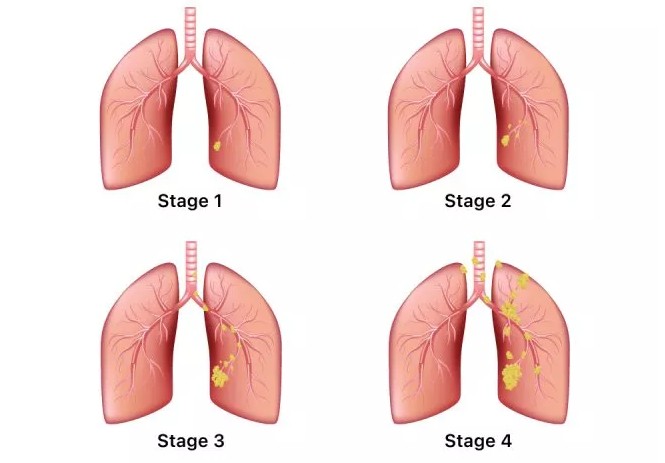

폐렴 증상 폐렴은 폐의 세균, 바이러스, 곰팡이 등 감염으로 인해

폐포(폐 속의 공기 주머니)에 염증이 생기고, 고름이나 액체가 차는 질환입니다.